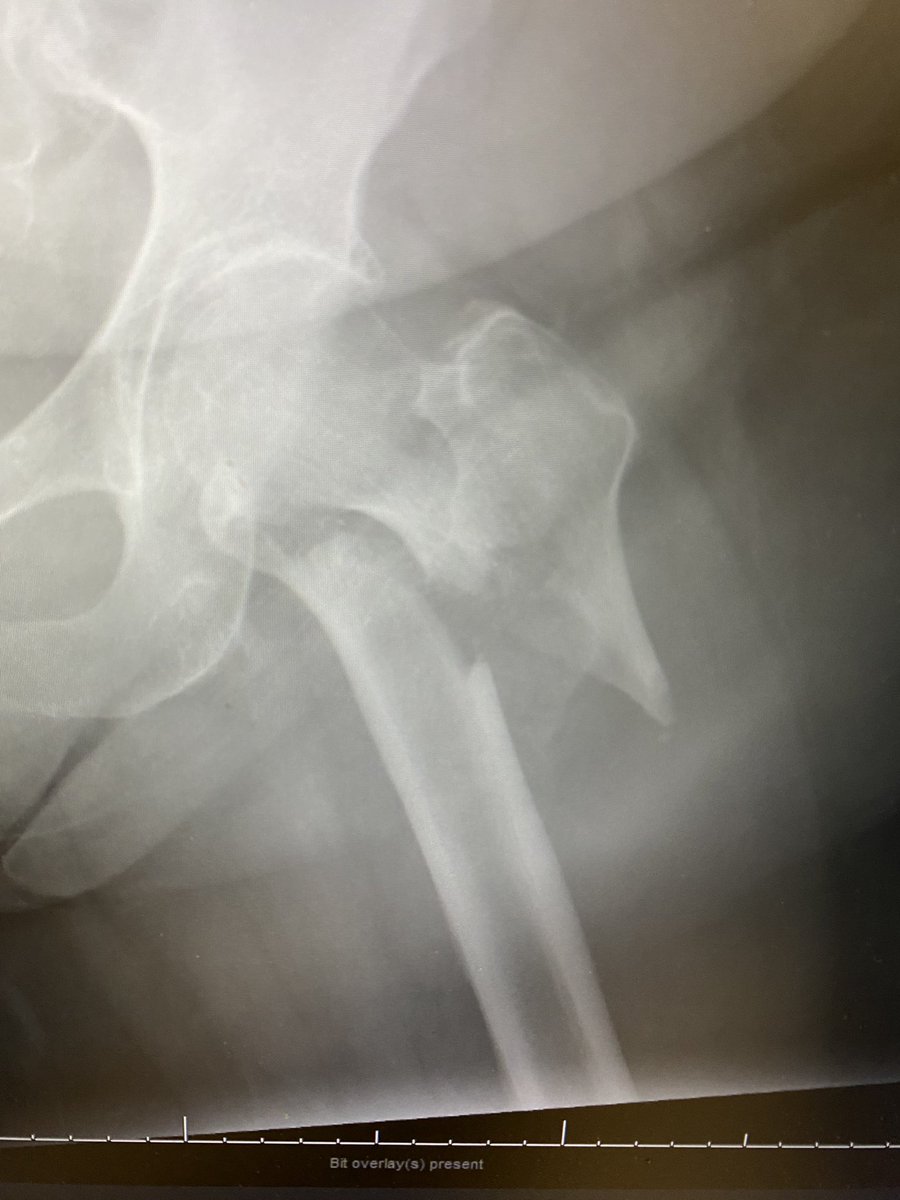

@sportsdoc2016 Even the interns know that this is a case to nail instead of DHS